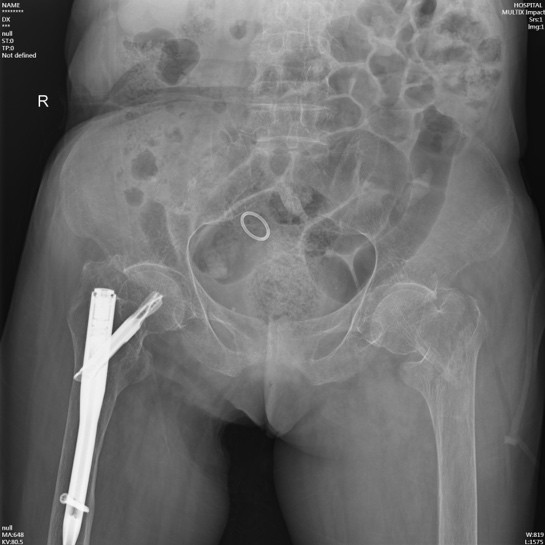

在詢問陳奶奶的家屬后得知,陳奶奶年事已高,疾病纏身,除了有冠心病、心房顫動、全心衰等心臟方面的問題,同時合并有老年性骨質(zhì)疏松、主動脈硬化、甲狀腺功能亢進(jìn)(未進(jìn)行治療)、貧血、凝血功能異常等基礎(chǔ)疾病。另外,陳奶奶曾于2020年在我院順利完成了“右側(cè)股骨粗隆間骨折閉合復(fù)位APFN內(nèi)固定術(shù)”,術(shù)后恢復(fù)良好,3年來生活基本恢復(fù)正常。

術(shù)前

入住我院骨傷科后,鐘水林主治醫(yī)師立即安排陳奶奶完善各項(xiàng)術(shù)前檢查??紤]到陳奶奶高齡同時合并有較多的基礎(chǔ)疾病,有些疾病并未系統(tǒng)規(guī)范治療,如甲亢疾??;圍手術(shù)期風(fēng)險較大,我科組織全院大會診:邀請心血管科、內(nèi)分泌代謝病科、重癥醫(yī)學(xué)科、麻醉科等進(jìn)行術(shù)前討論和評估;結(jié)合患者病史,評估患者病情,充分討論后,鐘水林主治醫(yī)師與陳奶奶家屬進(jìn)行了充分溝通,為其量身定制了最佳的治療方案,對其骨折采取微創(chuàng)閉合復(fù)位手術(shù)治療(APFN)。

手術(shù)前